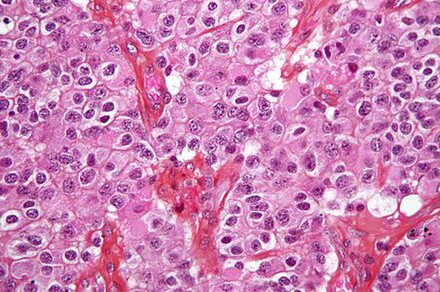

Brain & Spinal Cord Tumors

Brain and central nervous system tumors are the second most common cancers in children, making up about 26% of childhood cancers. There are many types of brain tumors, and the treatment and outlook for each is different.